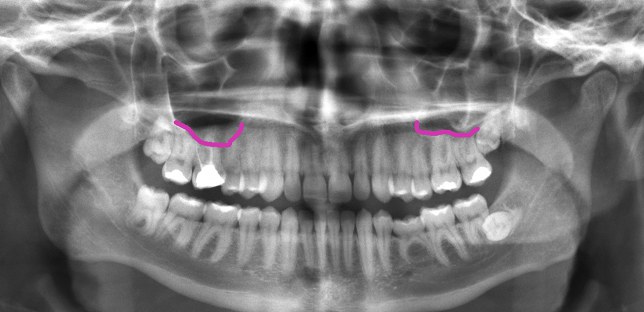

یک دنداندرد سینوسی ممکن است خیلی شبیه به دنداندردی باشد که در گذشته داشتهاید و به سینوسهایتان بیربط بوده است. بنابراین ملاقات با دکتر دندانپزشک و گرفتن عکس رادیوگرافی میتواند نشان بدهد که دندانتان مشکلی از قیبل پوسیدگی یا عفونت دارد یا خیر. یک پزشک هم میتواند سینوزیت را تشخیص بدهد و آن را با آنتیبیوتیکها و دکونژستانهای بینی از بین ببرد.